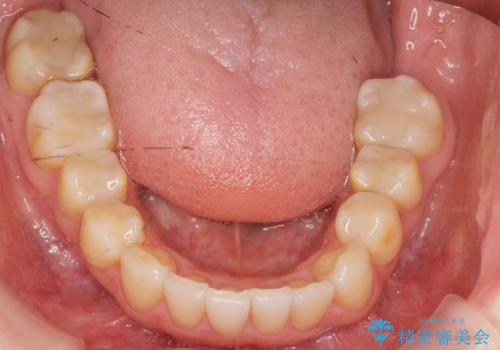

矯正装置:インビザラインフル (初回13stage+リファインメント11stage:計1年)

矯正後、右上5左上45セラミッククラウン・右下65左下5セラミックインレーによる補綴治療を行いました。

ご希望のマウスピース矯正で歯並びが綺麗になり、大変喜んで頂けました。

治療後には笑うと見えて気になっていた銀歯も白くなり、より一層素敵な笑顔を見せて下さいました。

ホワイトニング予定のため、セラミッククラウンの色は隣在歯よりやや白めにオーダーしました。